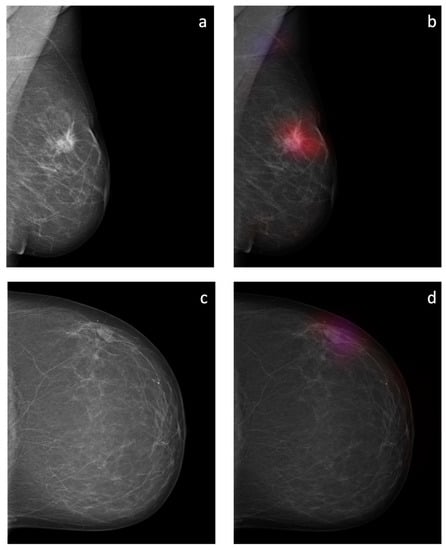

Figure 8. Overlay images of the calculated probability maps (b,d) created by the sliding window approach and the corresponding mammographic images (a,c) of two patients from the test dataset. In (a,b), a suspicious soft tissue opacity is highlighted in red. An area of denser tissue in the left axilla is correctly highlighted as a healthy tissue in blue. In (c,d), a probably benign soft tissue opacity is highlighted in purple.

3.3. Probability Maps

The sliding window approach was able to correctly detect the areal distribution of the suspicious soft tissue opacity. Excellent image quality could be obtained. Examples of probability maps are shown in (Figure 8).